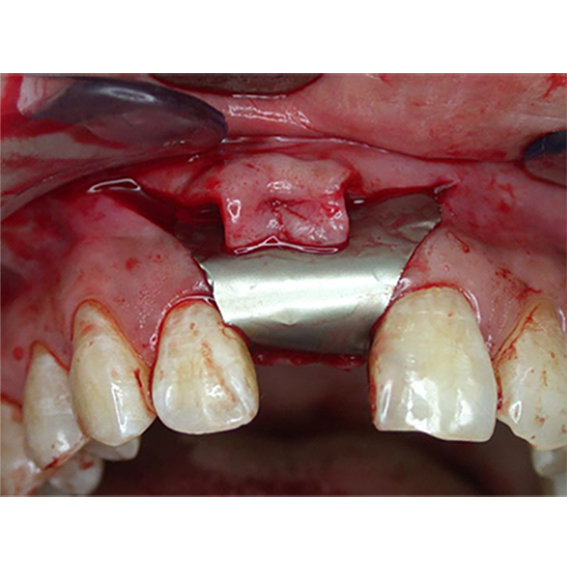

Pure titanium membrane of ultra-thin thickness of about 10 microns (0.01mm). Totally inert, biocompatible and non-biological thus removing the fear of disease transmission from collagen of bovine source. It allows ease of handling and adaptation over the operative site. Because of its mouldability, it does not require pin or screw fixation, thus avoiding the risks of pin or screw swallowing or aspiration. Excellent clinical performance in guided tissue regeneration. Resistance to infection after exposure. Primary wound closure is not necessary. No tissue reaction or wound infection.